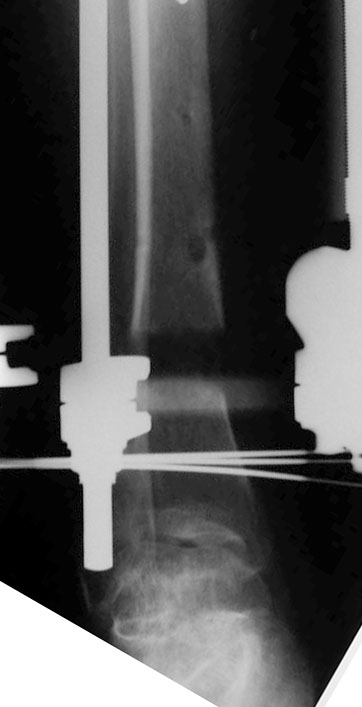

S/P Frame

Frame

Halt Trans

Regen Closeup

Placed on 6 wk course IV Ancef. (same pan sensitive bug at debridement). CRP, ESR normalized. Presently off abx. with no clinical signs of infection other than he's not making regenerate. I've halted transport and waited 4 wks with no real change. Any suggestions when not seeing regenerate. Any suggestions on stimulating regenerate? Thanks in advance for the input.